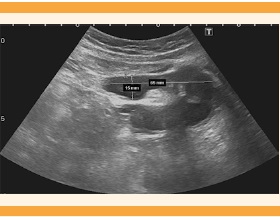

En la ecografía abdominopélvica se sospechó una malformación congénita uterina, pues se visualizó el útero izquierdo ligeramente tubular, de tamaño normal, con un pólipo endometrial en su interior, y adyacente a la imagen se observó una masa compatible con hemiútero derecho, de 52 x 49 mm, con contenido líquido hematológico retenido (hematometra) de 25 mm. El hemiútero no tenía conexión aparente con el cuello uterino ni con la porción contralateral del útero (Figura 1). El ovario izquierdo se visualizó de tamaño y características normales, con microfolículos y eje mayor de 3.2 cm, rodeando por fuera y por delante al ovario derecho, también de tamaño y aspecto normales; se observó una estructura quística alargada y en forma de codo, con contenido ecogénico de 65 x 15 mm, sugerente de hematosalpinx (Figura 2). La tomografía abdominopélvica confirmó la coexistencia del hemiútero derecho, de 55 x 54 mm, hipervascular, degenerado, con colección hemorrágica interna de 30 mm (Figura 3), e hidrosalpinx derecho. La ecografía y la tomografía no demostraron malformaciones renales. Figura 4

Figura 2 Hematosalpinx que rodea al ovario derecho; se observa una estructura quística alargada y en forma de codo, con contenido ecogénico, de 65 x 15 mm, sugerente de hematosalpinx.